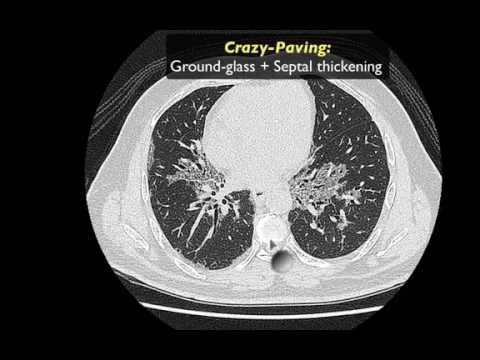

Radiology Viva Cases # 139-143 | Chest Exam Cases Part -1 #medical #radiology #ultrasound #doppler